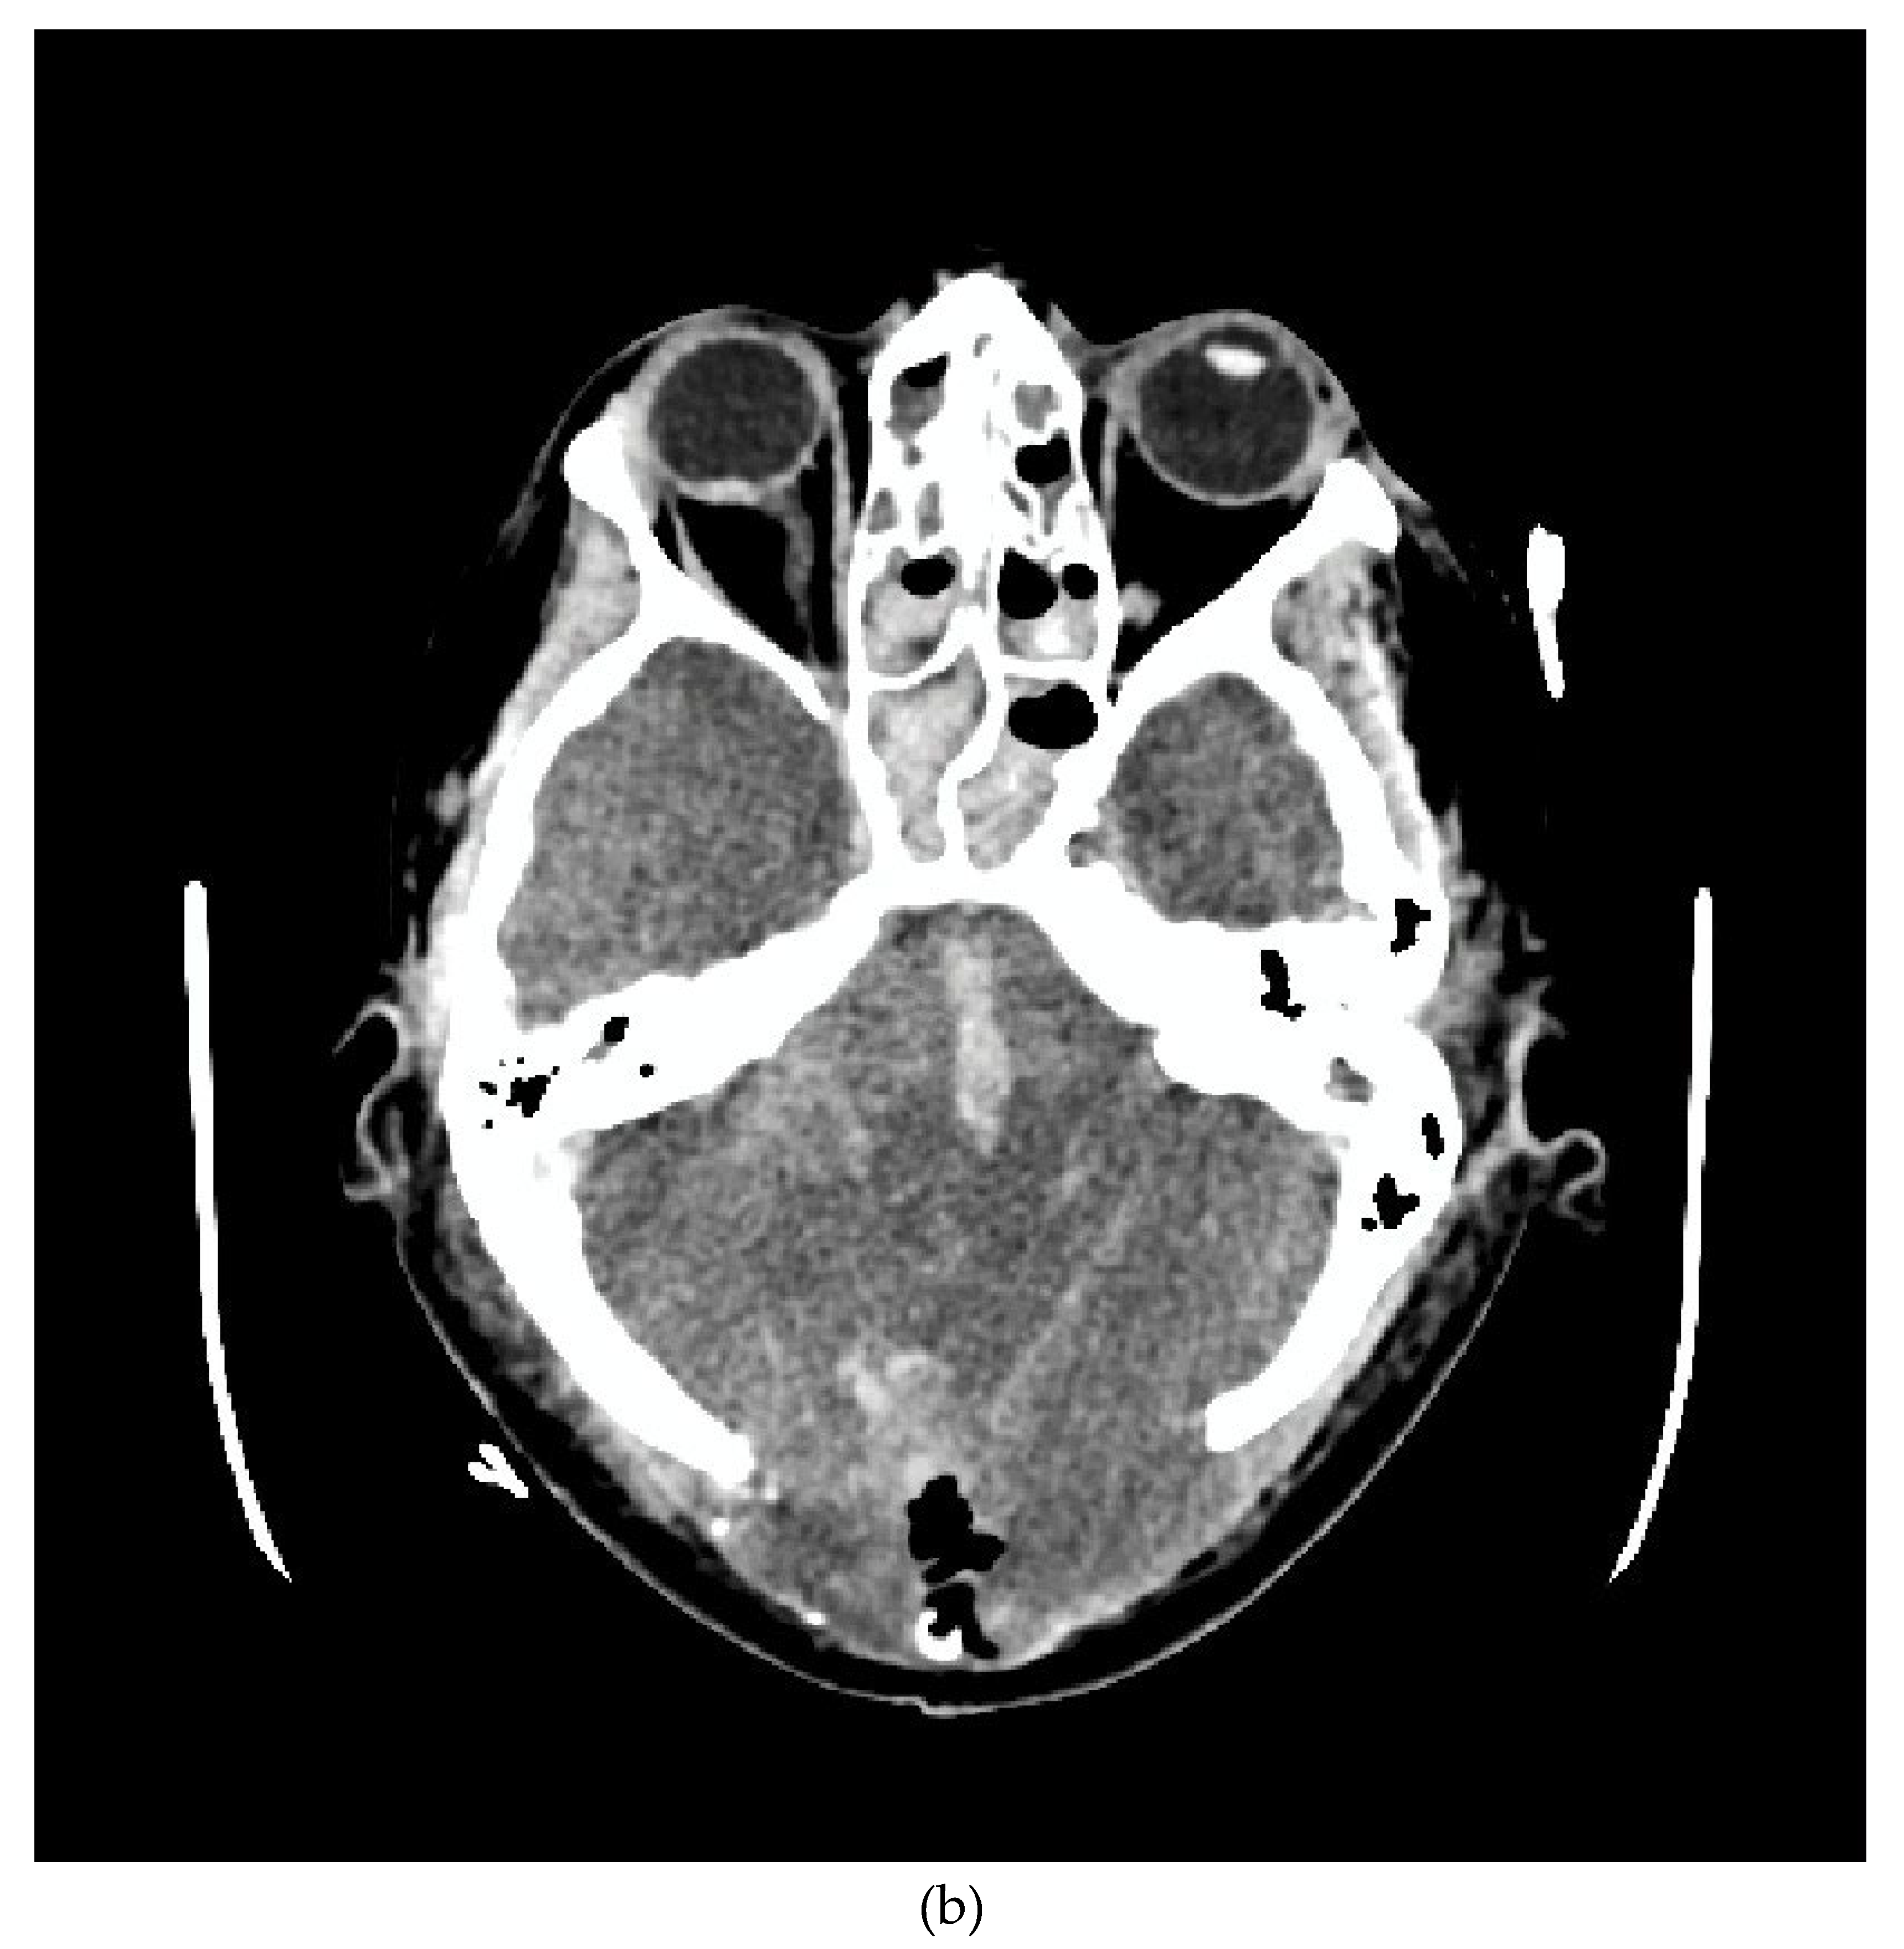

We present the case of a 33-year-old female patient with a diagnosis of AML (Acute Myeloblastic Leucaemia). The patient, was transferred from Haematology Unit to ICU following neurological deterioration. On the basis of the imaging studies performed, the diagnosis was an acute intracranial haemorrhage. Immediately after the CT scan, the patient underwent neurosurgical treatment. After the surgical procedure, he was readmitted to the ICU. Despite the therapy, the patient was diagnosed with the absence of brain reflexes. Among the imaging tests performed, there was a CT scan of the CNS (Figure 1a,b) and CTA (Figure 2a,b), which showed catastrophic brain damage. Then, according to institutional brain death guidelines clinical evaluations and apnoea tests were performed at certain intervals (Current AAN brain death guidelines do not require multiple exams) [10].

Figure 1. Head CT. The examination shows intermediate features of severe cerebral ischaemia. (a) Loss of grey/ white matter differentiation in the supratentorial space with a sign of pseudosubarachnoid haemorrhage. (b) Severe oedema of the posterior fossa structures (despite suboccipital decompression), with completely obliterated basal cisterns and ischaemic-haemorrhagic changes in the brainstem.